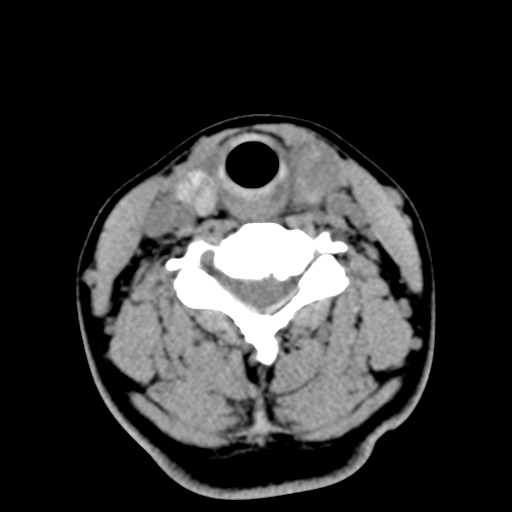

女,44岁,左颈部肿块伴疼痛两个月。患者不能做增强扫描。

左侧甲状腺明显肿大,密度不均匀性减低,正常之钙化基本消失,残留少许呈云雾状及颗粒状。其边缘不规则、不清晰,与前部联合处正常甲状腺不能分界不清,但尚可与周围其他组织分辨。颈动脉鞘区无明显淋巴结肿大。

多考虑:左侧甲状腺癌。

左侧甲状腺明显肿大,密度不均匀性减低,可见明显淋巴结肿大.

考虑:左侧甲状腺癌

左侧甲状腺癌可能性大。